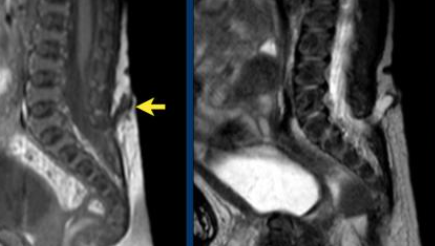

Moelel basse attachée

- Cône se terminant en dessous de L2

- Filum terminale épaissit

- Peut être associée à une myéloméningocèle ou un lipome du filum terminale